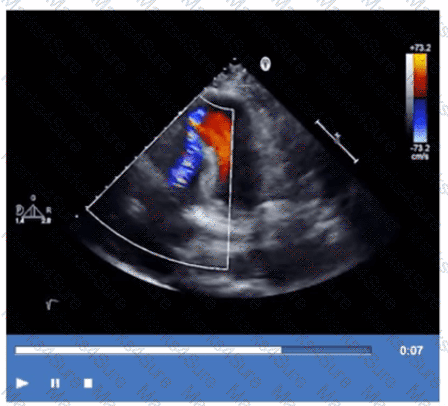

Which Doppler signal is most consistent with significant aortic valve regurgitation?

Which next step is appropriate after obtaining the Doppler signal in this image?